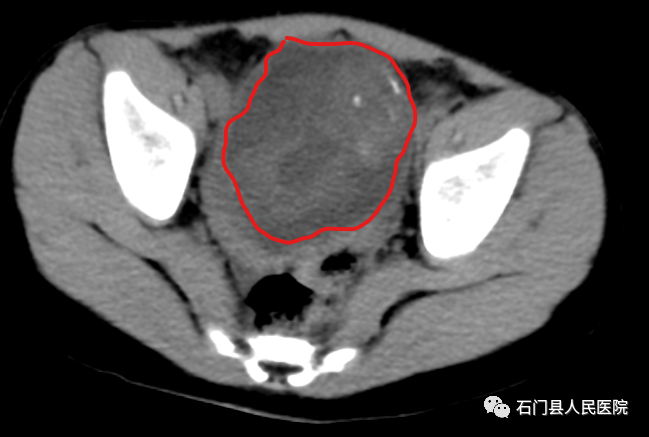

家人吓坏了,赶紧带乐乐来我院就诊,在我院进行腹部CT和腹部彩超,提示盆腔内有一个巨大肿块,考虑卵巢肿瘤,建议住院手术治疗。

收治入我院妇科22病区后,病区主任周美浓集合科室全体医师行疑难病例讨论,结合乐乐的辅助检查资料,考虑右侧卵巢卵黄囊瘤可能性大。

做好充分术前准备后,妇科团队为乐乐进行了手术。术中发现右附件有一直径约7厘米大小的包块,椭圆形,表面光滑无赘生物,无破口,右附件扭转180度,行开腹右附件切除术+大网膜活检。

我院病理科接到标本后,迅速进行术中冰冻诊断,结果为恶性肿瘤。术后病理科诊断医师巨检见右侧卵巢大小约6×5×4cm,囊实性肿块,可见油脂。镜下小部分区域见不典型的疏松网状结构、內胚窦小体(S-D小体,肾小球样血管袢)、圆形或者卵圆形的嗜酸性透明小体、成熟的软骨及呼吸道黏膜腺上皮和鳞状上皮组织等,结合免疫标记AFP(+)及较高的细胞增殖指数Ki67表达和其他相关肿瘤标记表达阴性,结合组织形态学明确诊断为混合性生殖细胞肿瘤,主要成分为卵黄囊瘤,合并部分成熟性囊性畸胎瘤。